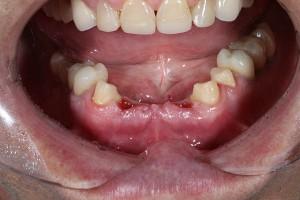

- Если отсутствует один или несколько зубов.

- При полной адентии.